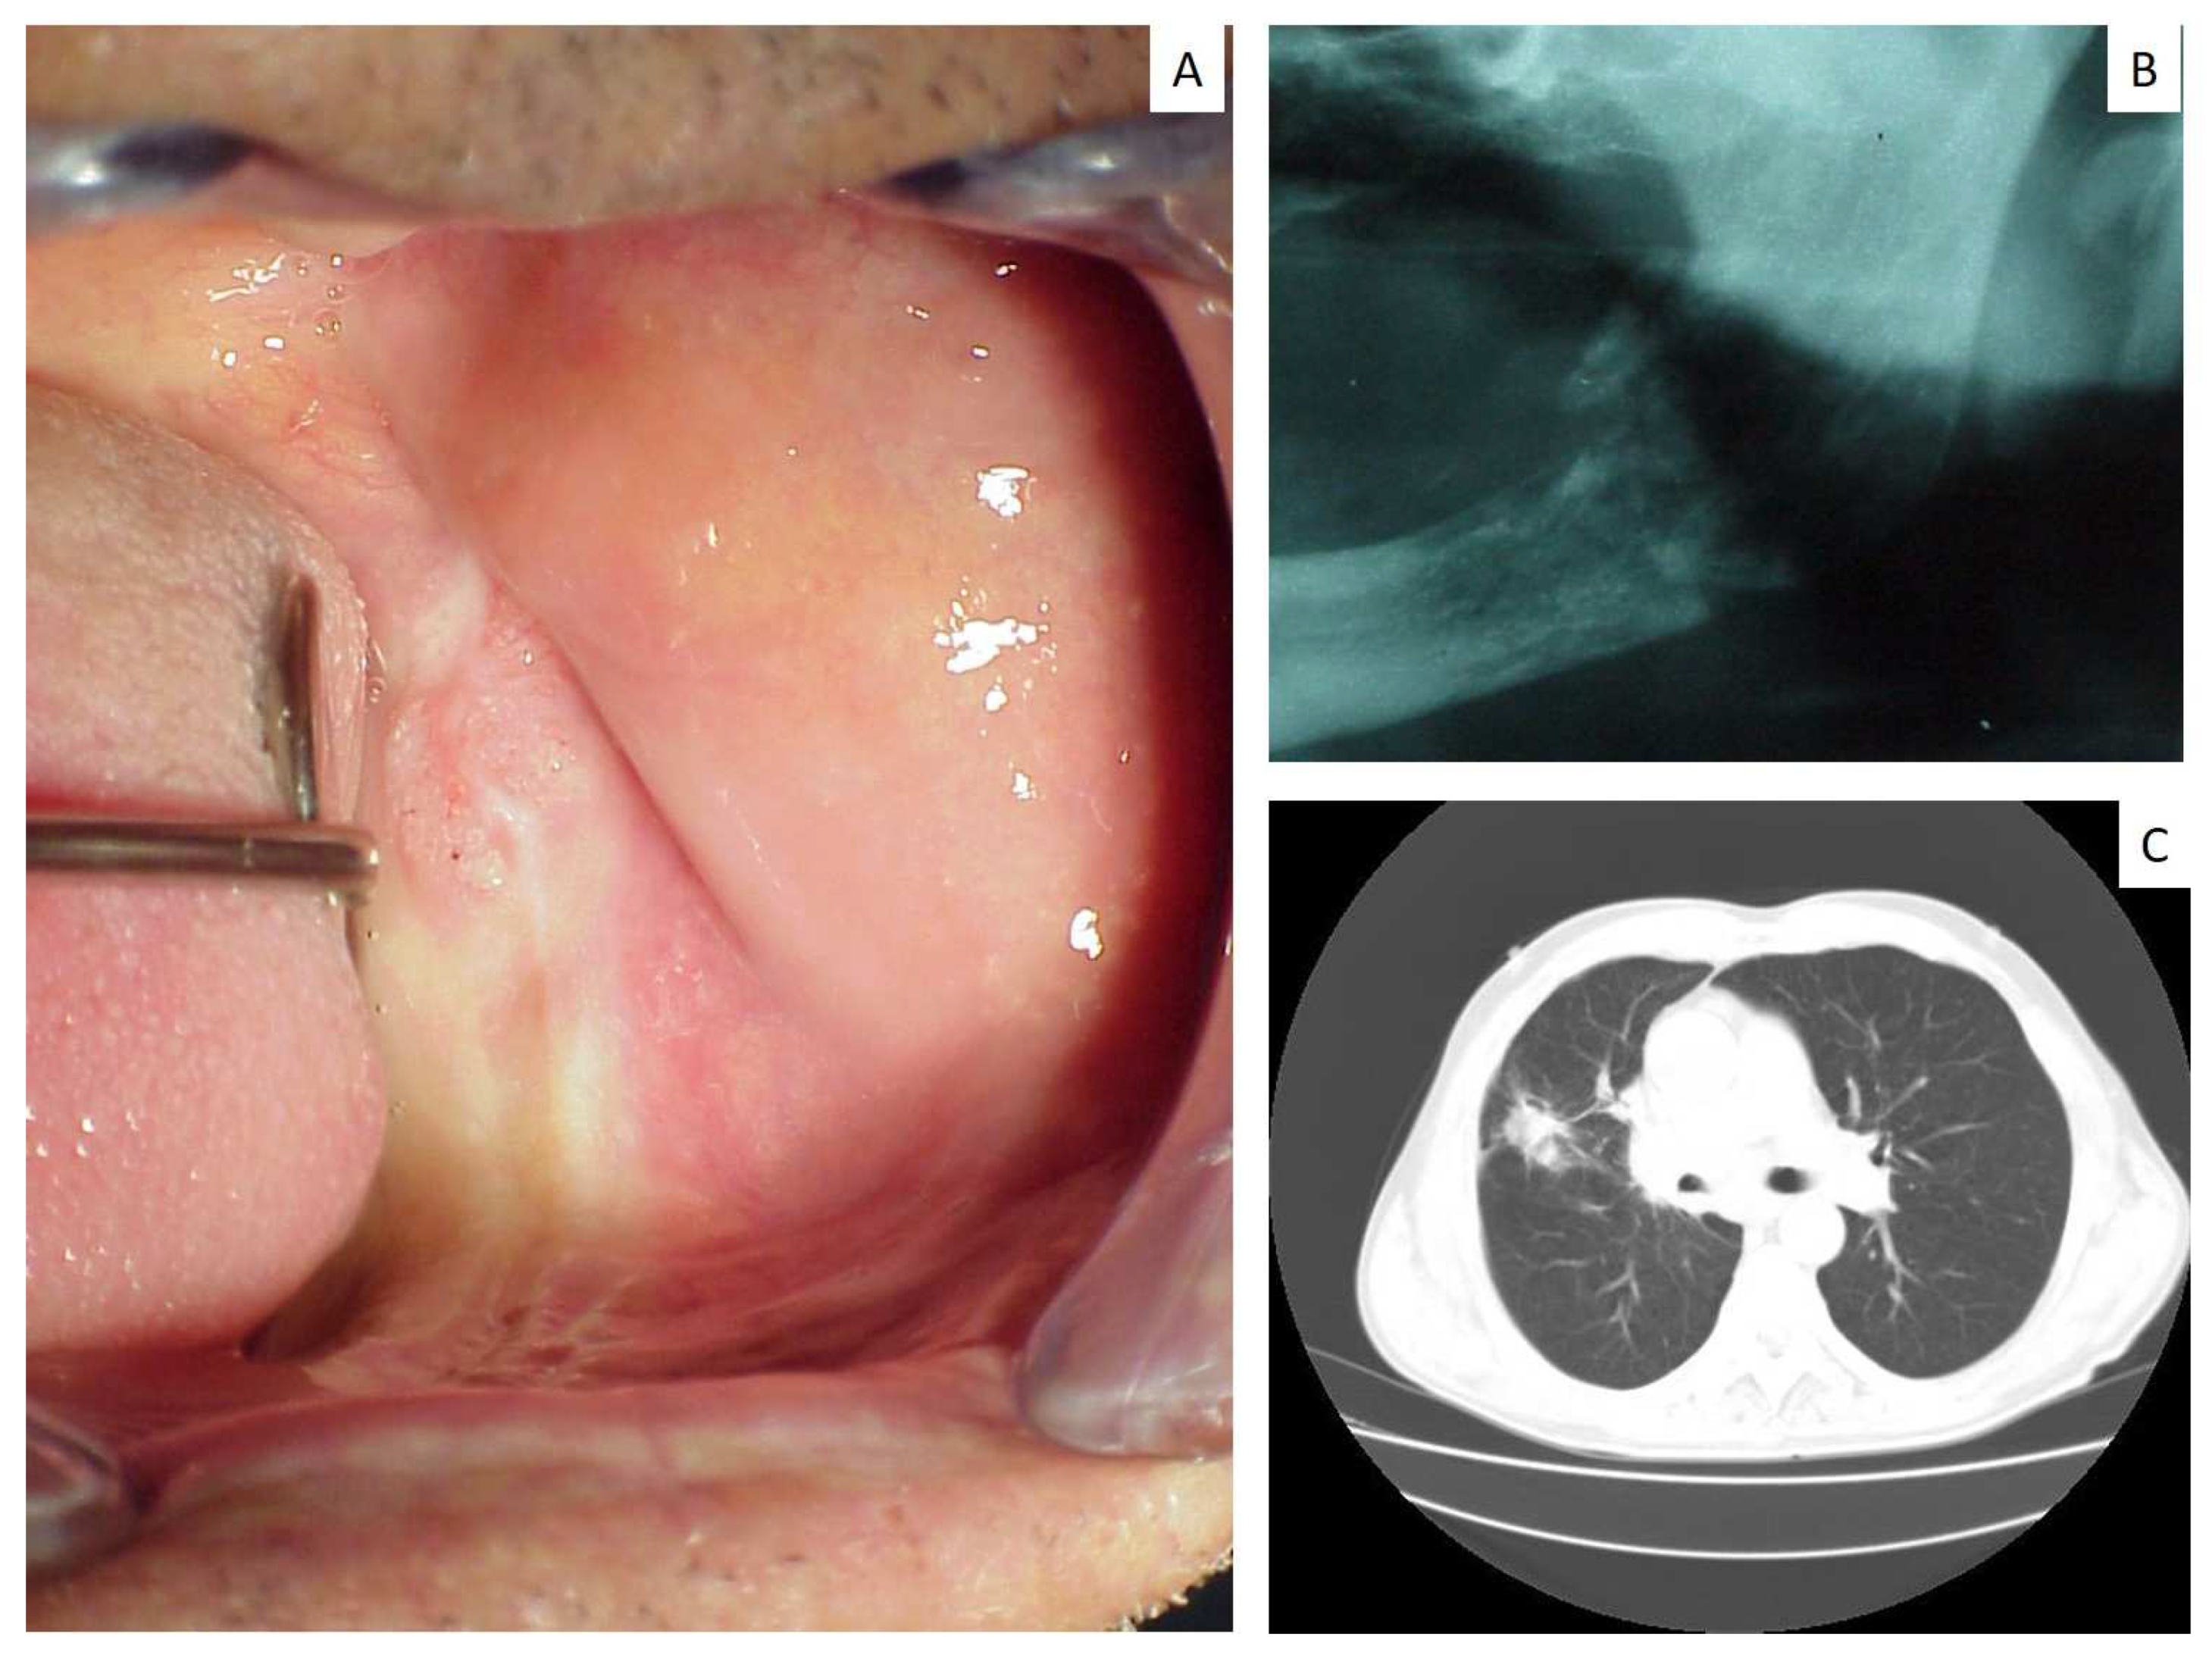

| 10 | 79 | M | Gingiva/palate | Non small cell carcinoma | n.a. | Yes |

| 15 | 67 | M | Maxillary gingiva | Squamous carcinoma | Vertebra | No |

| 16 | 65 | M | Parotid gland | Small cell carcinoma | n.a. | Yes |

| 17 | 70 | F | Maxillary gingiva Around dental implant | Small cell carcinoma | n.a. | Yes |